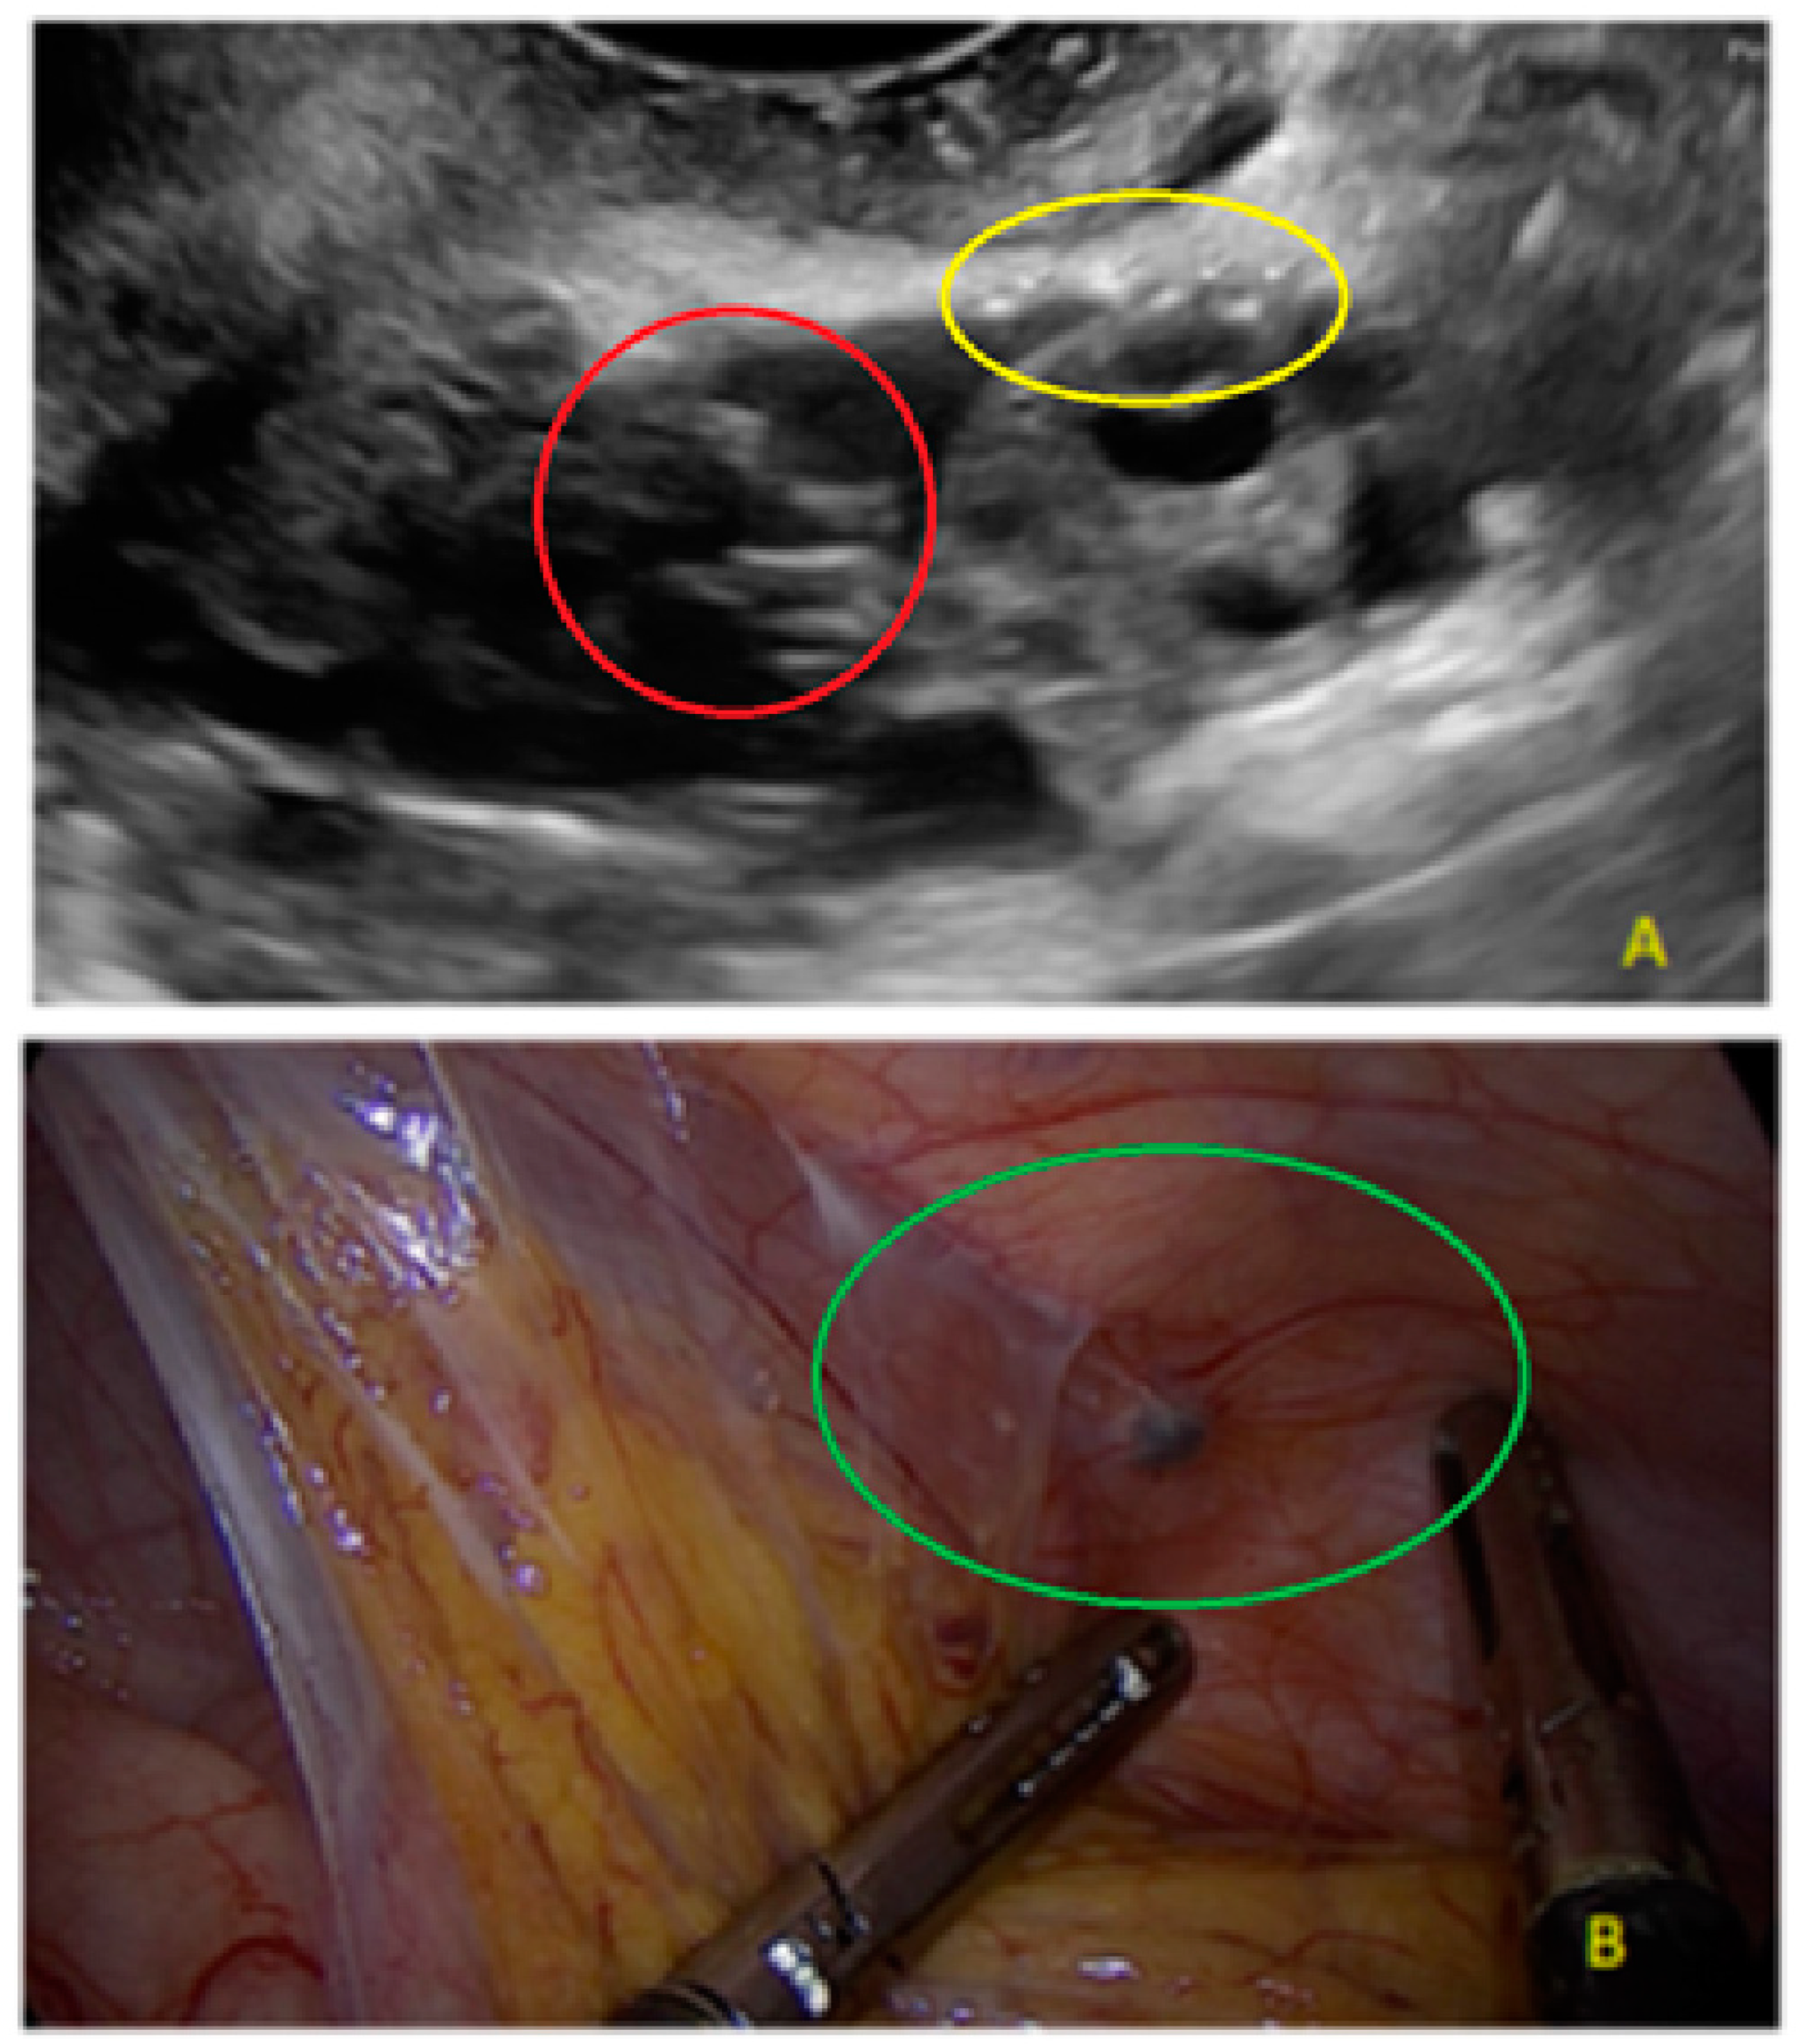

- The presence of hypoechogenic associated tissue (hypoechoic areas surrounding a small cyst area; we called this a “hat”). This tissue does not protrude or invaginate the peritoneal surface.

- The lesion may be convex, protruding from the peritoneal surface into the peritoneal cavity (we called this “bulging”), or it may appear as a concave defect in the peritoneum (we called this a “pocket”).

4. Discussion